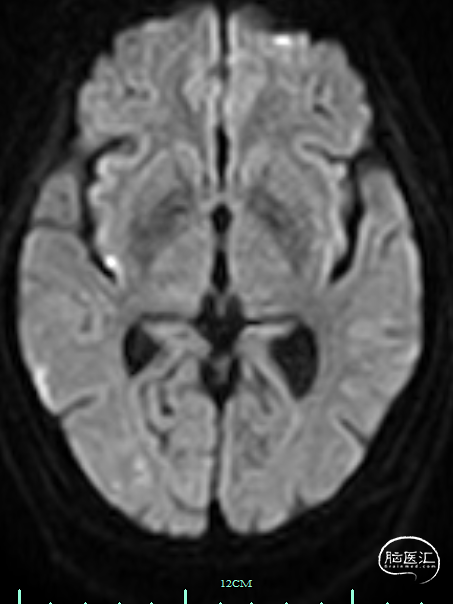

术前影像资料